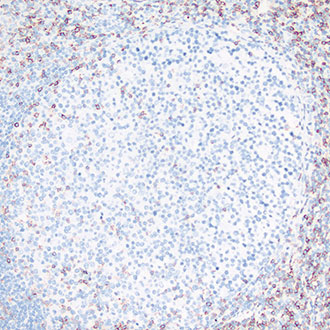

bcl-2

bcl-2 -